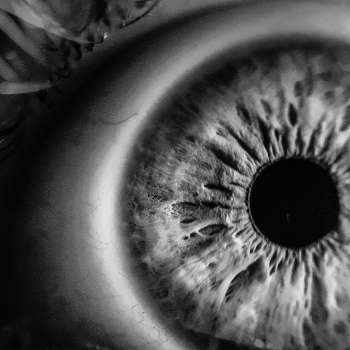

망막색소변성증은 망막의 망막색소상피세포가 손상되어 시력 저하를 일으키는 질환입니다. 이 질환은 주로 노인들에게 발생하며, 조기에 발견되지 않으면 심각한 시력 장애로 이어질 수 있습니다. 망막색소변성증의 주요 증상과 관련된 10가지 사항은 다음과 같습니다.

-망막색소변성증의 가장 두드러진 증상 중 하나는 시야 손실입니다. 이 질환은 주로 중심 시야를 침범하므로, 환자들은 시력이 흐려져 가장자리 시야가 감소하는 것을 느낄 수 있습니다. 처음에는 선명도가 감소하는 것으로 느껴질 수 있으며, 시간이 지남에 따라 가장자리 시야의 손실이 더욱 두드러지게 나타날 수 있습니다. 이는 환자들이 일상 생활에서 세밀한 작업이나 더 넓은 시야가 필요한 활동을 수행하는 데 어려움을 겪게 합니다.

망막색소변성증은 환자들이 빛에 예민해지고, 광선에 민감해지는 현상을 유발할 수 있습니다. 빛이 강할 때 환자들은 눈이 아프거나 혐오감을 느낄 수 있습니다. 또한 일반적인 조명이나 밝은 태양빛을 피하는 경향이 있으며, 어두운 환경에서 시력이 훨씬 더 나아질 수 있습니다. 이러한 증상은 일상생활에서 불편함을 유발할 수 있으며, 환자들은 안경이나 선글라스를 착용하여 눈을 보호하는 것이 도움이 될 수 있습니다.

-망막색소변성증으로 인해 망막에 손상이 발생하면 환자는 대상을 정확하게 인식하지 못하거나 흐릿하게 보일 수 있습니다. 이중 시야를 경험하는 것은 일상생활에서 많은 불편함을 유발할 수 있으며, 환자는 사물을 인식하거나 거리를 판단하는 것이 어려울 수 있습니다. 특히 운전 중에 이러한 증상이 발생하면 교통사고의 위험을 증가시킬 수 있으므로 주의가 필요합니다. 이러한 증상은 시간이 지남에 따라 악화될 수 있으므로 조기에 진단하고 관리하는 것이 중요합니다.

-망막색소변성증 환자는 때때로 안구통을 경험할 수 있습니다. 이는 눈이 따끔거리거나 아프게 느껴지는 것으로 나타날 수 있습니다. 이러한 통증은 눈이 지나치게 들뜨거나 자극을 받을 때 특히 심해질 수 있습니다. 또한 눈물 분비가 증가할 수 있으며, 눈물이 눈에 자주 찰 수 있습니다. 이는 환자가 눈을 마주칠 때 불편함을 느끼게 할 수 있으며, 때로는 시력을 방해할 수 있습니다.

-망막색소변성증 환자는 어두운 환경에서 시력이 더욱 악화되는 경향이 있습니다. 어두운 곳에서 환한 빛을 구별하기 어려워지며, 눈의 빛 감응이 떨어져 시야의 선명도가 줄어듭니다. 이는 밤에 운전을 할 때나 어두운 실내 공간에서 활동할 때 더 큰 불편함을 유발할 수 있습니다. 어두운 환경에서의 시력 악화는 환자들이 안전한 환경에서 일상생활을 유지하는 데 어려움을 겪게 합니다.

-망막색소변성증은 주로 중심 시야를 영향을 주므로, 환자들은 세밀한 작업을 수행하는 데 어려움을 겪을 수 있습니다. 가령, 책을 읽거나 작은 물체를 보는 것이 어려울 수 있으며, 선명한 이미지나 글씨를 인식하는 데 어려움을 겪을 수 있습니다. 이러한 증상은 일상생활에서 환자들에게 불편함을 유발하며, 종종 환자들은 돋보기나 확대 도구를 사용하여 중심 시야의 선명도를 향상하려고 합니다.

-망막색소변성증은 안구 건조 증후군의 증상을 야기할 수 있습니다. 안구 건조는 눈이 건조하고 따끔거리는 느낌을 유발하며, 때로는 눈이 물리거나 붉어질 수 있습니다. 망막색소변성증으로 인한 시력 감소는 눈을 과도하게 사용하거나 눈이 지나치게 길어지는 경우에도 나타날 수 있습니다. 이러한 증상은 환자의 삶의 질을 저하시키며, 일상 활동에 불편함을 초래할 수 있습니다.

-망막색소변성증은 색상 인지에도 영향을 미칠 수 있습니다. 환자들은 색상의 명도와 대비를 인식하는 능력이 저하될 수 있으며, 때로는 색깔이 희미하거나 탁한 것으로 보일 수 있습니다. 특히 어두운 곳에서 이러한 변화가 두드러질 수 있으며, 일상생활에서 색상을 구별하는 데 어려움을 겪을 수 있습니다. 예를 들어, 교통 신호나 색이 중요한 작업을 수행할 때 더 큰 어려움을 겪을 수 있습니다.

-망막색소변성증은 안구의 혼탁감과 흐릿한 시야를 유발할 수 있습니다. 이는 환자가 주변 환경을 제대로 인지하지 못하고, 시야가 일그러지거나 흐릿하게 보일 수 있습니다. 특히 환자가 움직이거나 빛이 강한 환경에서 시야가 더욱 혼란스러워질 수 있습니다. 이러한 증상은 일상 생활에서 환자들에게 불편함을 유발하며, 안전한 환경에서의 활동을 제한할 수 있습니다.

-망막색소변성증은 운전 및 다양한 일상 생활 활동에 영향을 줄 수 있습니다. 시력 저하, 안구 건조, 색상 인지 변화 및 안구 혼탁감 등의 증상으로 인해 운전 시 주의력과 반응 속도가 저하될 수 있습니다. 안구 건조로 인해 시력이 흐려지고, 색상 인지 변화로 신호나 표지판을 인식하는 능력이 감소할 수 있습니다.

또한 안구 혼탁감으로 인해 도로나 교통 상황을 제대로 파악하기 어려울 수 있습니다. 뿐만 아니라 일상생활 활동에서도 이러한 증상들이 불편을 초래할 수 있습니다. 색상 인지 변화로 인해 작업이나 취미 활동에서 어려움을 겪을 수 있으며, 안구 건조와 혼탁감으로 인해 글을 읽거나 컴퓨터 작업을 하는 데 어려움을 겪을 수도 있습니다. 또한 망막색소변성증으로 인해 생기는 안구 불편감은 환자들의 일상생활에 부정적인 영향을 미칠 수 있으며, 일상적인 활동에 대한 자신감을 저하시킬 수 있습니다.

따라서 망막색소변성증 환자들은 운전 및 일상 생활 활동을 수행할 때 특별한 주의가 필요합니다. 증상의 심각성과 정도에 따라 안전을 위해 운전을 자제하거나 보조 운전자를 통해 운전을 하는 것이 중요할 수 있습니다. 또한 안구 건조 및 혼탁감 관리를 위한 적절한 치료 및 안내가 필요하며, 일상생활 활동에서 발생하는 어려움을 최소화하기 위해 안구 건강에 유의해야 합니다.

이러한 증상은 망막색소변성증의 진행 정도와 환자의 개인적인 상태에 따라 다를 수 있으며, 증상이 나타나는 정도와 빈도가 서로 다를 수 있습니다. 종종 이러한 증상들은 환자들의 삶의 질을 저하시키고, 일상 생활에서의 활동을 제한할 수 있으므로, 적절한 치료와 관리가 필요합니다.